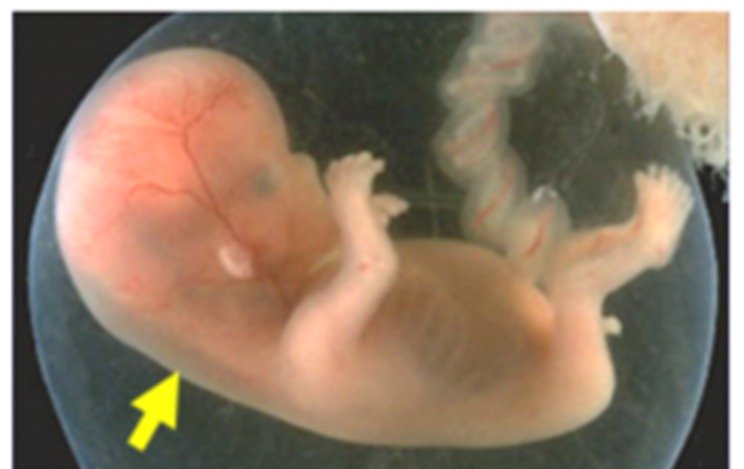

The baby’s crown-rump length (CRL) should measure between 45 mm and 84 mm for accurate NT measurement.

- Early fetal anatomy (brain, abdominal wall, limbs)